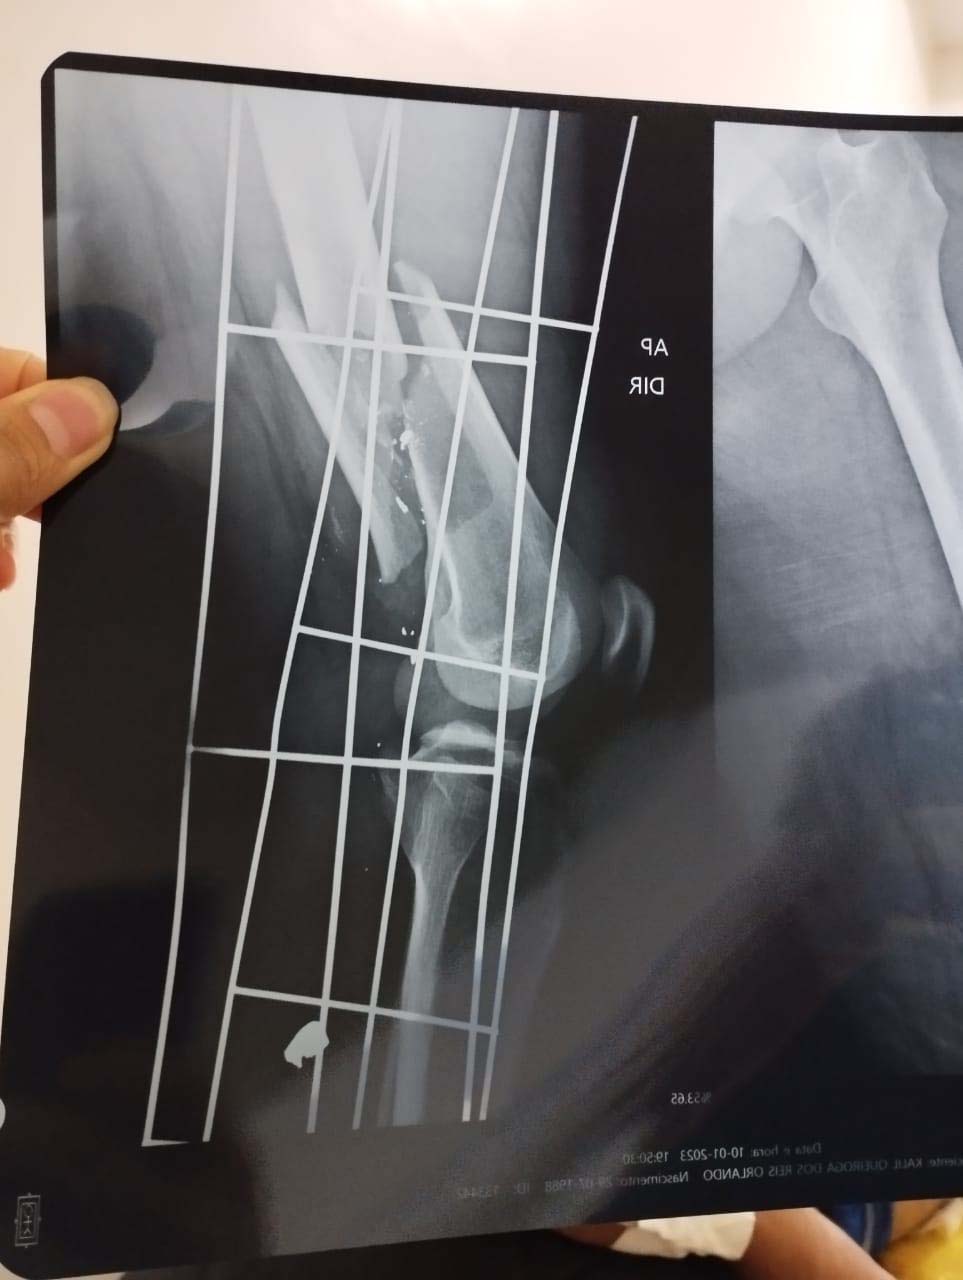

Kalil Queiroga sofreu uma fratura do fêmur, lesão no nervo responsável pelo movimento do pé, e lesão na veia arterial na altura do joelho, onde se formou um coágulo impedindo o fluxo sanguíneo chegar até o pé.

A primeira cirurgia foi realizada no SUS (Sistema Único de Saúde). A segunda cirurgia do fêmur da perna foi realizada no hospital particular no valor de R$ 15.600,00 (quinze mil reais e seiscentos reais). Já a terceira cirurgia, na veia artéria, ficou no valor de R$ 43.000,00 (quarenta e três mil reais).

Mesmo com as três cirurgias não foi possível salvar a perna do jovem Kalil Queiroga, sendo necessária uma quarta cirurgia para amputar a perna, que teve custo de R$ 12.500,00 (doze mil e quinhentos reais), totalizando o valor R$ 71.100,00 (setenta e um mil e cem reais).